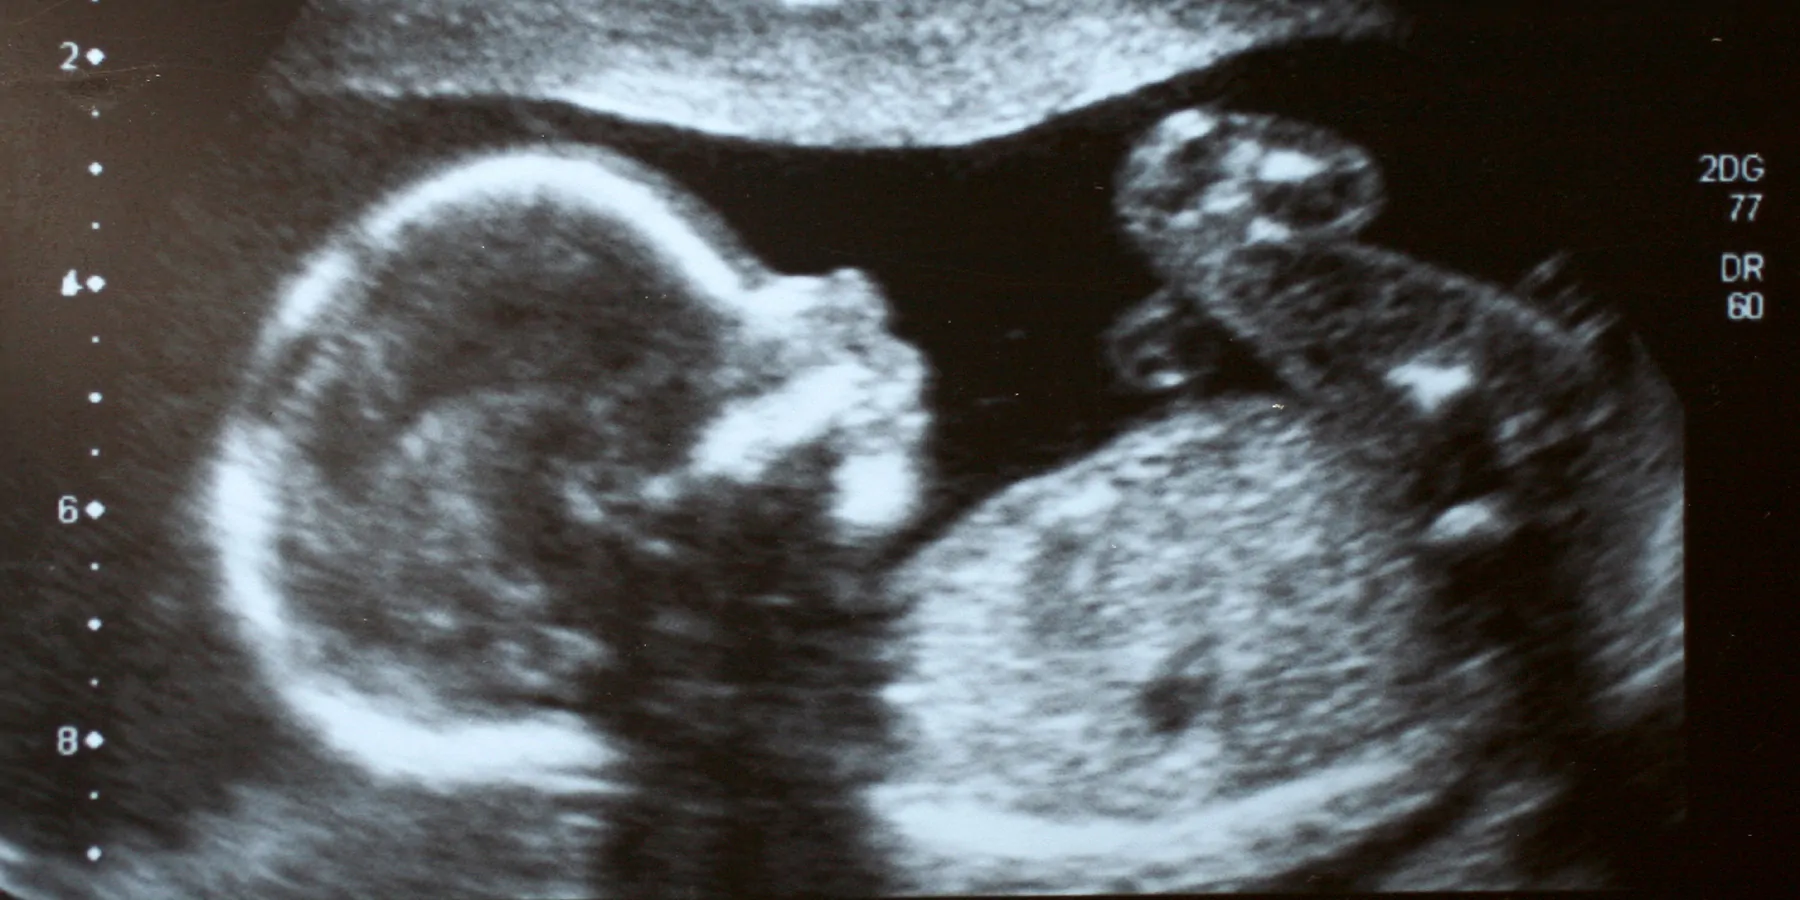

CHICAGO, IL — The exclusion of pregnant patients in initial COVID-19 vaccine clinical trials left many patients and doctors wondering how the vaccine might affect pregnant patients and their unborn babies. A new Northwestern Medicine study has found the vaccine is not associated with birth defects that are detectable on ultrasound.

The types of birth defects the scientists were looking for on the study participants’ ultrasounds were ones they deemed “major fetal structural anomalies,” such as the baby’s heart not forming correctly or the spine not closing properly. In the United States, 3 to 5 percent of births are impacted by these types of defects, resulting in increases in infant morbidity, mortality, and billions of dollars in cost.

The study analyzed electronic medical records (including ultrasounds and COVID-19 vaccination records) from a cohort of 3,156 pregnant people who received a complete fetal anatomical survey (19-week ultrasound) at Northwestern Medicine Prentice Women’s Hospital between March and November 2021. Of those pregnant patients, 2,622 (83.1 percent) received at least one vaccine dose and 1,149 (43.8 percent) were vaccinated inside of the scientists’ defined vaccination window (30 days prior to conception until 14 weeks gestational age).